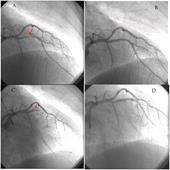

Khi chụp mạch vành, bác sĩ của bạn sẽ chỉ cho bạn thấy động mạch vành bị hẹp/tắc, vị trí tắc nghẽn và mức độ tổn thương, có cần phải can thiệp nong và đặt stent hay không. Tên và nhánh của các động mạch vành được chỉ ở hình 1.

Khi thuốc cản quang được bơm vào động mạch vành. Động mạch sẽ được hiện lên ở trên một màn hình đặc biệt. Khi thấy lòng mạch máu bị tắc hoặc hẹp, bác sỹ sẽ tiến hành nong và đặt stent tại vị trí hẹp.